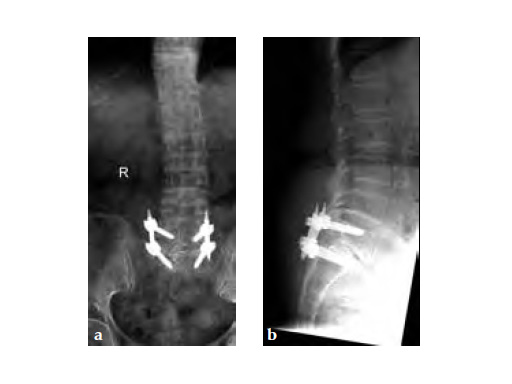

The patient underwent left L5S1 minimally invasive TLIF with pedicle screws 2 years ago for left lumbar 5th radiculopathy. At the same time she was put on fosamax for osteoporosis.

Case provided by Merng Koon Wong, Singapore, Singapore

Three weeks prior to her last admission, she complains of recurrent right thigh pain for which epidural analgesics were administered for presumed radiculopathy, however preliminary x-rays and even MRI of the thigh were also taken in view of her primary complaint regarding her right thigh. These investigations did not indicate the possibility of impending bisphosphonate related femur fracture. It is clear from the radiographs that she has an obvious anterolateral bow of her femur and a thickened lateral cortex in the lateral midshaft cortical bone, which may indicate a stress fracture (see Fig 3a-b).

No edema indicated a stress fracture (see Fig 4a-b).